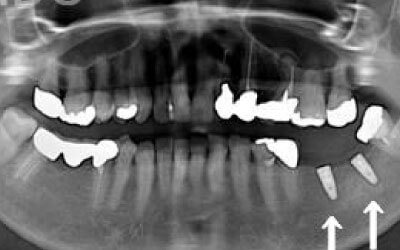

CTでは、骨や歯の状態を三次元で確認でき、正確な距離を測定することができます。

骨の厚さや傾き、神経の位置などを事前に詳しく計測することで、安全にインプラントを行うことができます。

骨が薄い場合、そのままインプラントを行うのはお勧めできません。

ただし、事前に骨を増やす治療を行ったり、インプラントと同時に骨を増やす治療をすることで、インプラントは可能です。

しかし、事前にCTでしっかりと撮影し、三次元的に神経との距離を計測して治療計画を立てることで、心配は不要です。

また、当院では削りすぎを防ぐためのストッパーも使用しています。

4)骨の状況をしっかり把握するためにも、CT撮影が必須となります。